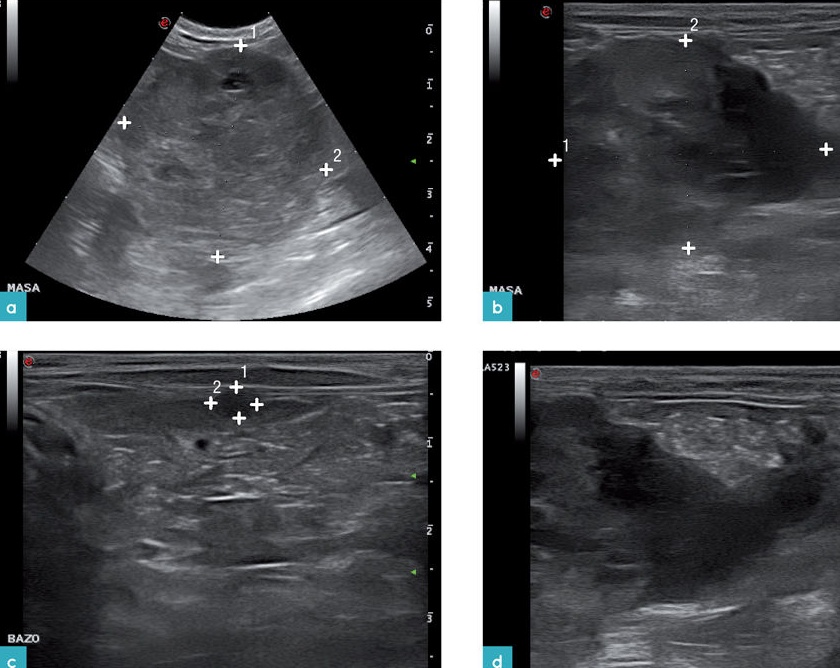

비장의 국소적 병변은 실질내 편만하게 에코성의 변화가 있는 것 보다 쉽게 발견됩니다(그림 8). 국소적 혹은 여러 국소적인 비장 결절들은 개와 마찬가지로 고양이에서도 흔하지 않습니다. 발생 시에는 정상 비장의 실질보다 등에코성 내지 저에코성을 보입니다.

(c) 11세 중성화된 수컷 고양이에서 림프종(lymphoma)으로 인해 이질적인 비장 종양(화살표)이 관찰됨. 복부 내 림프절 비대와 소량의 복수도 확인됨.

(d) 12세 중성화된 암컷 고양이에서 암종증(carcinomatosis)과 관련된 비장 꼬리 부분에 크고 잘 경계된 종양(측정 캘리퍼 사이)이 존재. 종양은 나머지 비장 실질에 비해 등에코성을 보이며, 편심적으로 위치한 이질적인 무에코 영역 또한 있음. 3개월 전 시행한 초음파 검사에서는 비장이 정상으로 확인되었으며, 전이성 또는 가능성 있는 원발성 신생물성 비장 질환이 가장 가능성 높은 감별 진단으로 고려됨.